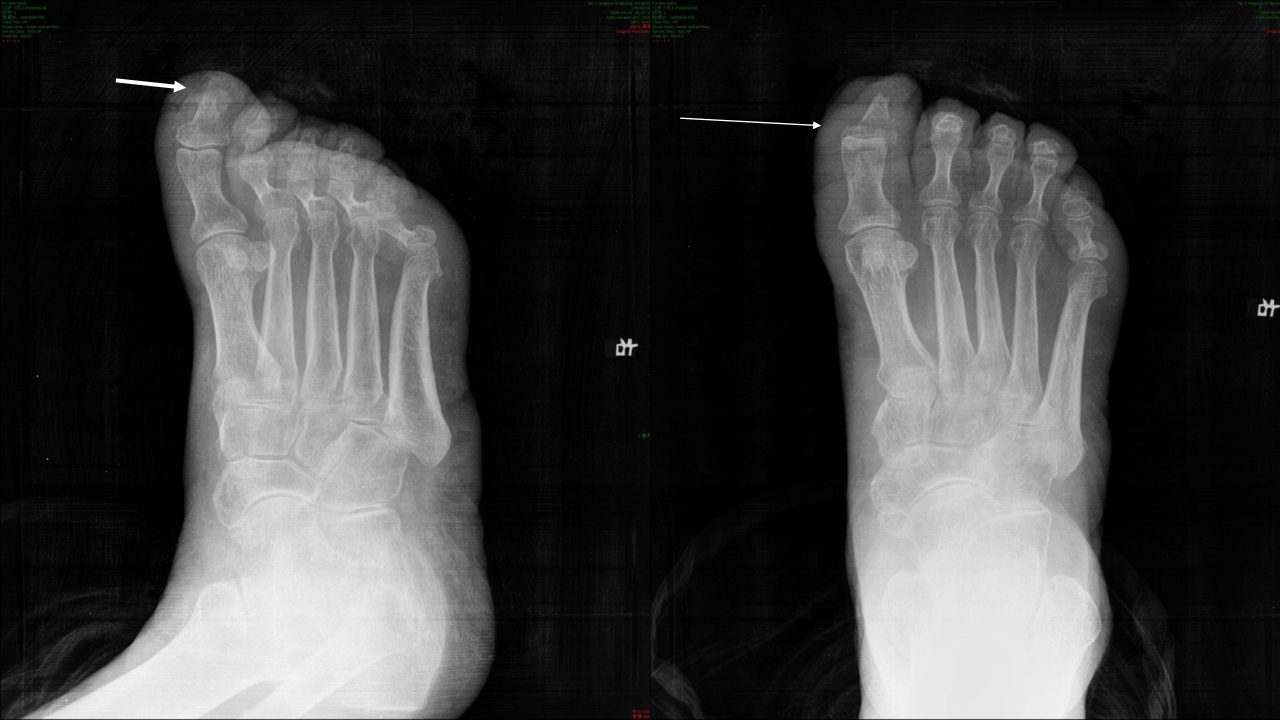

糖尿病足的治疗与护理 目录/content 一 糖尿病足的定义 二 糖尿病足发病机制及诊断? 三 糖尿病足如何治疗? 四 如何预防和护理糖尿尿足? 1 糖尿病足的定义 糖尿病足定义 糖尿病足:主要是与糖尿病下肢远端神经异常和不同程度的外 周血管病变相关的足部感染、溃疡和(或)深层组织破坏。 由于神经营养不良和外伤的共同作用,可引起Charot关节。 是糖尿病最严重的和治疗费用最高的慢性并发症之一。 糖尿病足流行病学资料 国外资料显示: 在所有因糖尿病住院的有关问题中,糖尿病足占到47%。 5%-10%糖尿病患者有不同程度足溃疡,1%的糖尿病患者截 肢。 糖尿病足是许多国家截肢首位原因。 中国糖尿病防治指南,2005,55 糖尿病足流行病学资料 在我国糖尿病足患病率占糖尿病患者的14%, ...